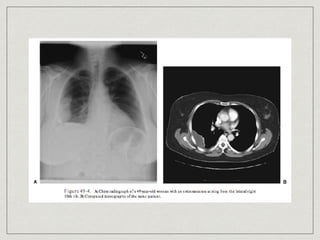

Chondrosarcoma

most common primary chest wall bone neoplasm

60% arises in costochondral arches or sternum

30-40 years old

cause is unknown

slow enlarging mass become painful

lobulated mass arising in medullary portion with

destruction of cortex and mineralization of tumor

matrix(mottled type of calcification)

treatment is complete resection, 5-yr survival of 64%

Chondrosarcoma most common primarychest wall bone neoplasm 60% arises in costochondral arches or sternum 30-40 years old cause is unknown slow enlarging mass become painful lobulated mass arising in medullary portion with destruction of cortex and mineralization of tumor matrix(mottled type of calcification) treatment is complete resection, 5-yr survival of 64%